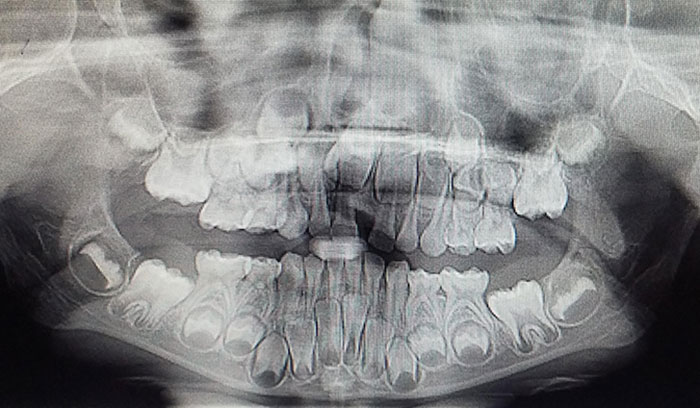

I Have A Rare Disorder Called Cleidocranial Dysotosis. Got My First Dental X-Ray Today And I Have A Lot Of Extra Teeth

X-Rays Of Children's' Mouths Between The Ages Of 6-12 Years Still Hold Wonder For Me, Even After Being A Dentist For 10+ Years

Panoramic X-Ray Of A Child (Adult Teeth Growing In)

Today I Took A Dental X-Ray For A Child. This Is How The Milk Teeth Change Permanently. The Picture Clearly Shows How The Premolar Comes Out